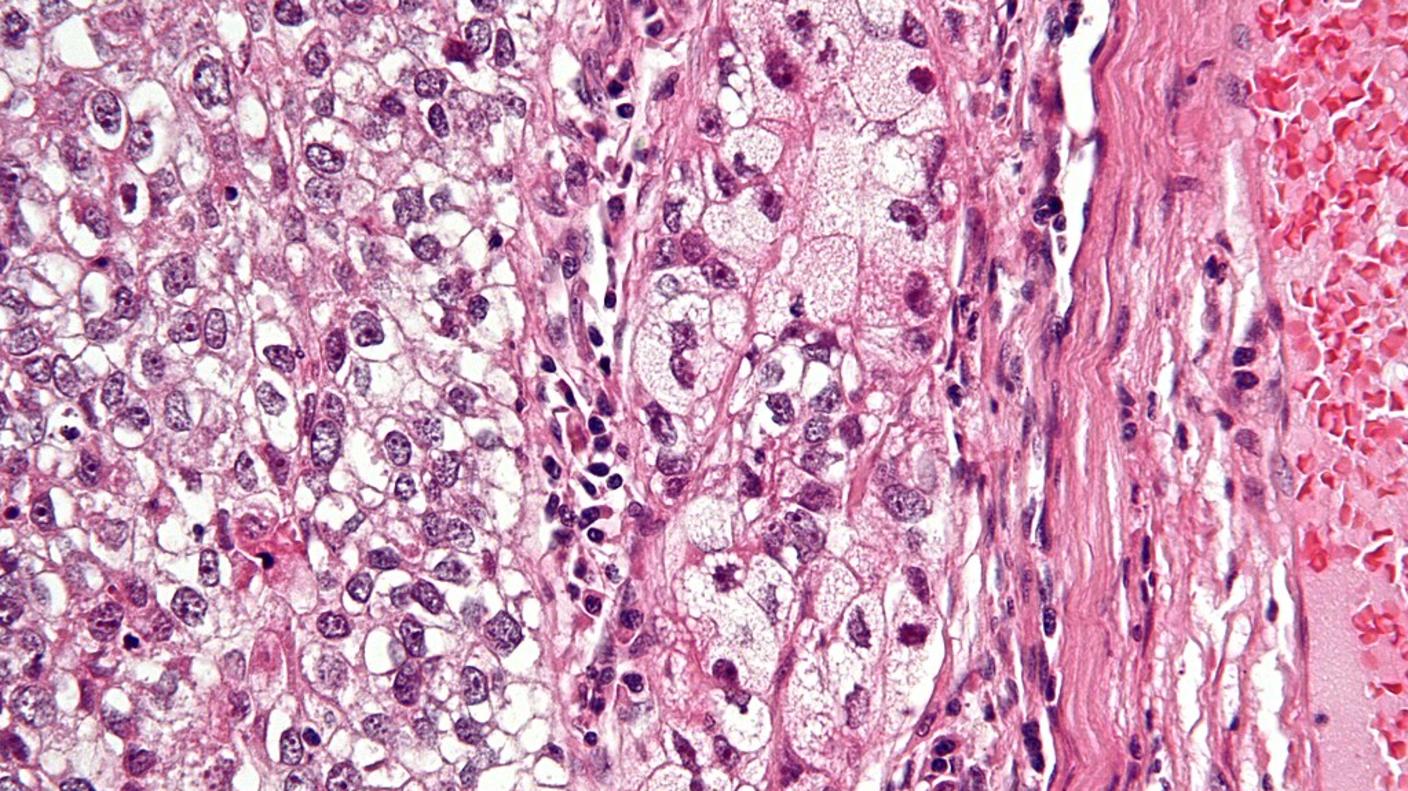

Genomic Landscape of Sebaceous Tumors

Study identifies key diagnostic and therapeutic targets for this rare, aggressive skin cancer.